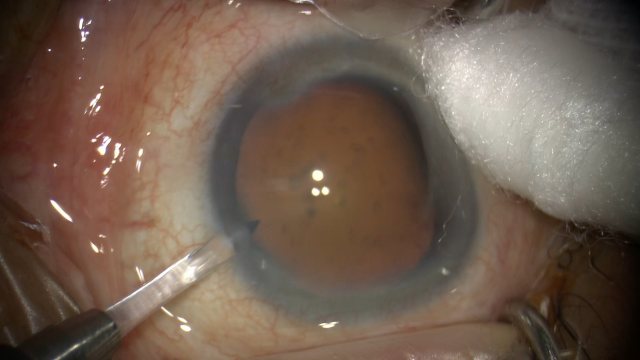

号外号外,湖南省人民医院副院长祖雄兵和眼科主任医师曾琦被指存在不正当关系,并有不雅视频传出。对此,医院工作人员回应:组织正在调查,请给医院宣传部门联系。当地卫生健康委员会对此回应:暂未接到相关的信访反映。祖雄兵为湖南省人民医院副院长,泌尿外科学科带头人。曾琦,博士,主任医师,硕士研究生导师。现任湖南省人民医院眼科副主任、眼科一病区主任,湖南省卫生健康高层次青年骨干人才,湖南省预防医学会眼病防治专业委员会主任委员、湖南省女医师协会眼科专业委员会主任委员、湖南省医学会眼科学专业委员会防盲学组副组长、湖南省医学会眼科学专业委员会眼外伤及职业病学组副组长、湖南省医学会眼科学专业委员会白内障学组副组长、